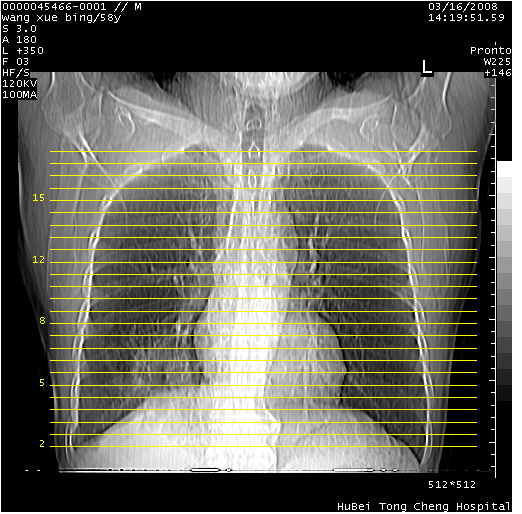

胸部cr x线片提示:1)右下肺脓肿。2)右下肺周围型肺癌不排除。建议:行ct扫描检查。

胸部ct轴位平扫(层厚10mm,螺距1.5,重建间隔10mm),图像如下: